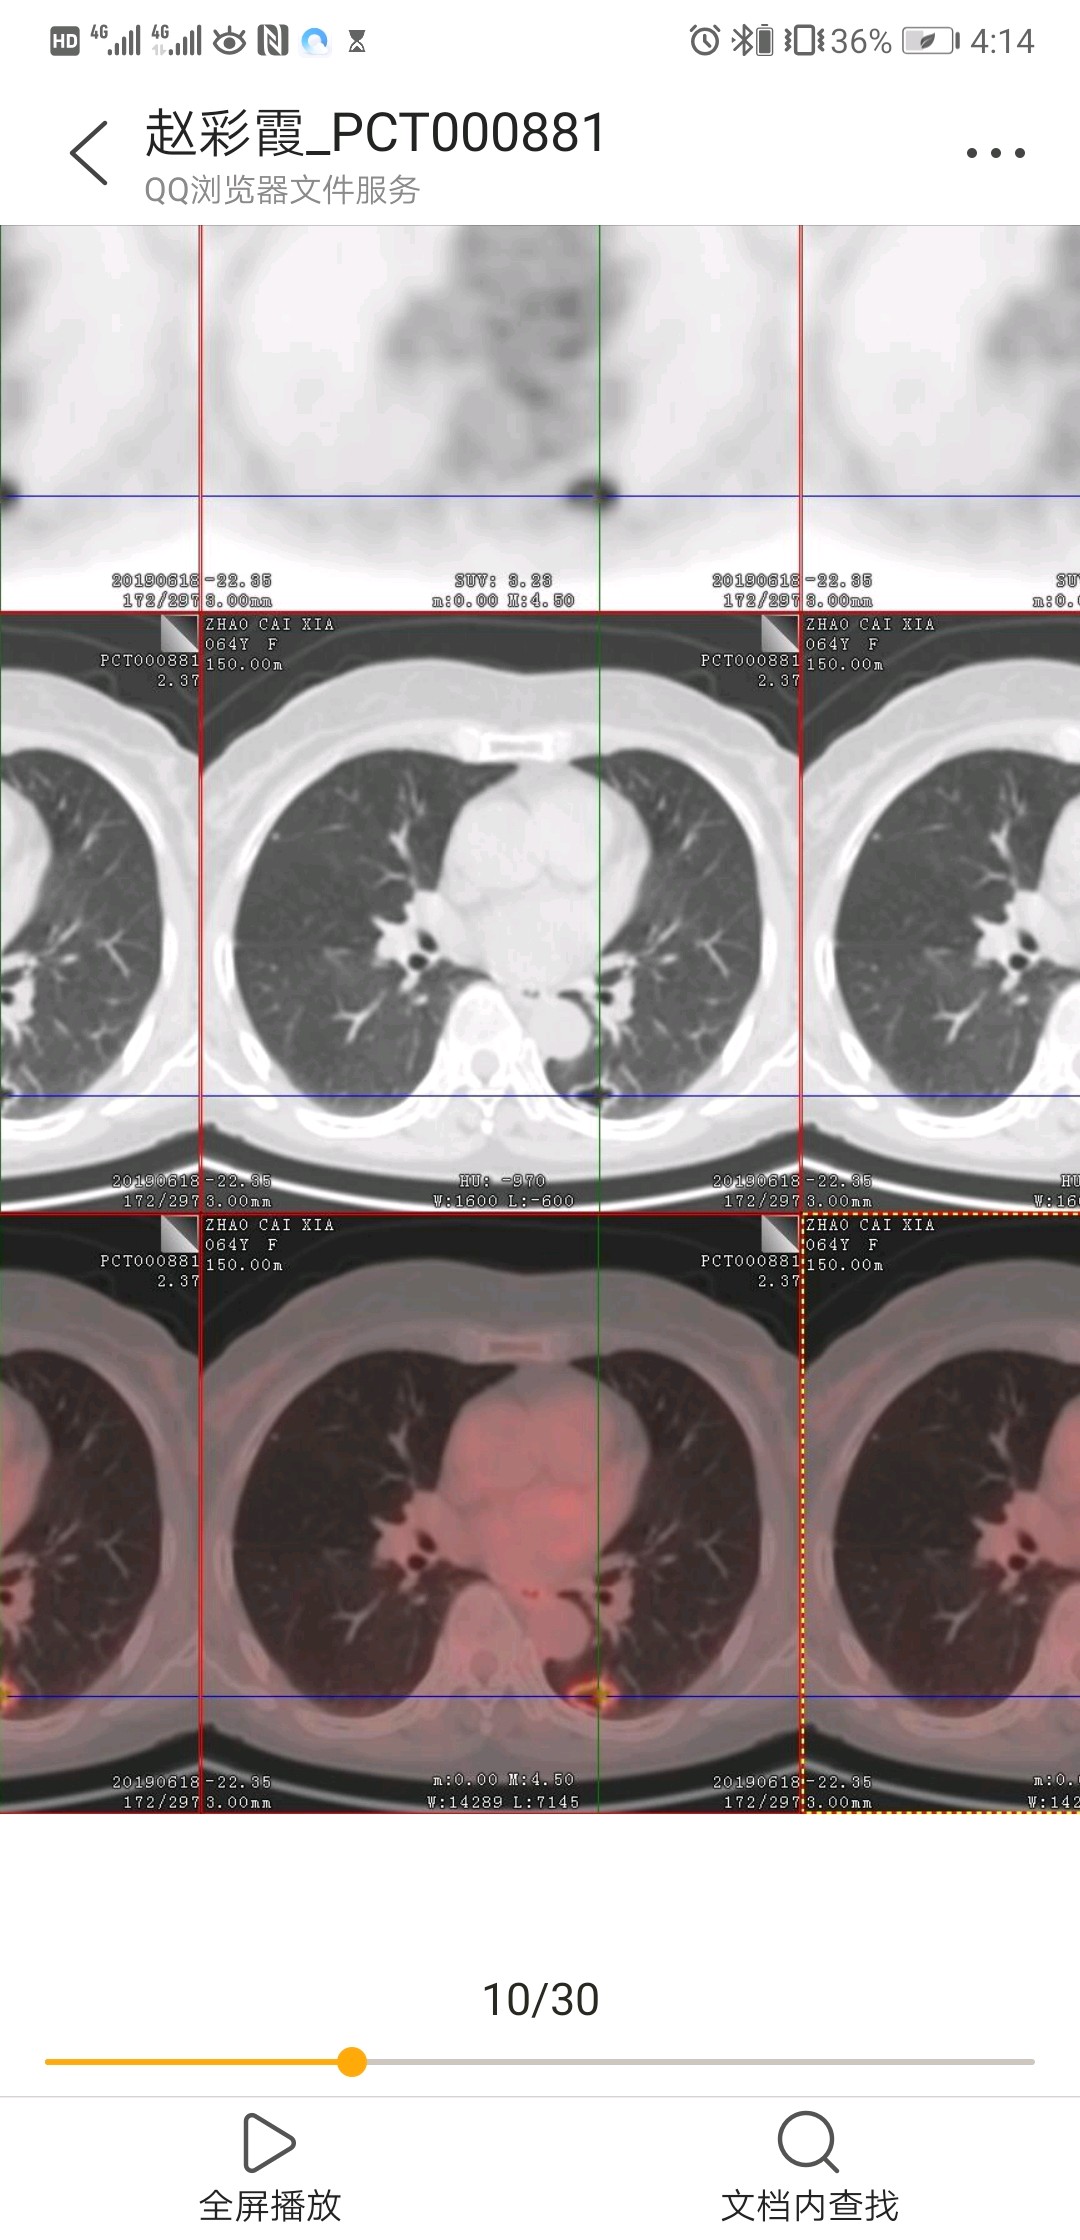

张阿姨(化名)5年前因咳嗽,确诊右上肺肺结核,按医生嘱咐坚持服用了一年的抗结核药物。一年后复查CT发现原来左下肺的小结节变成了小空洞,全面检查没有发现活动性肺结核依据,医生建议继续观察。连续三年肺部CT检查发现左下肺空洞逐步增大,壁较前增厚。张阿姨停药后一直没有咳嗽、咳血、消瘦等症状,平时注意锻炼身体,坚持每年体检。PET/CT提示左下肺空洞呈高代谢,肺门、纵膈淋巴结阴性,考虑周围型肺癌。

哪些病会表现为气囊?肺大疱、先天性囊性病变、结核和肺真菌病,以及肺癌、金葡菌感染等。由于肺癌晚期生存时间短,早诊早治是关键,发现肺内有肺大泡或肺囊肿,特别是“囊泡壁厚薄不均,囊内有细小分隔或血管影等征象”,务必加强随访,如果随访过程中出现囊腔扩大、囊壁局部或整体增厚、局限壁结节或外周肿块形成、腔内间隔、外壁毛刺或晕轮征等征象时要高度怀疑“囊性肺癌”的可能性。

关于囊性肺癌形成原因,一般认为癌瘤生长在小细支气管壁上,随着生长瘤体增大,使管腔完全阻塞,造成远端肺泡膨胀破裂,形成肺囊腔,癌组织支气管壁侵入囊腔形成壁结节影。